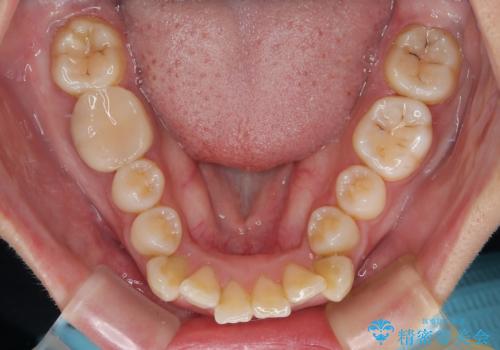

- 前歯のデコボコと口元の突出感を気にして来院された患者様です。

上下前歯がくちばしのように突出していたため、上下左右の第一小臼歯4本を抜歯し、ワイヤー装置にて矯正治療を行うこととしました。